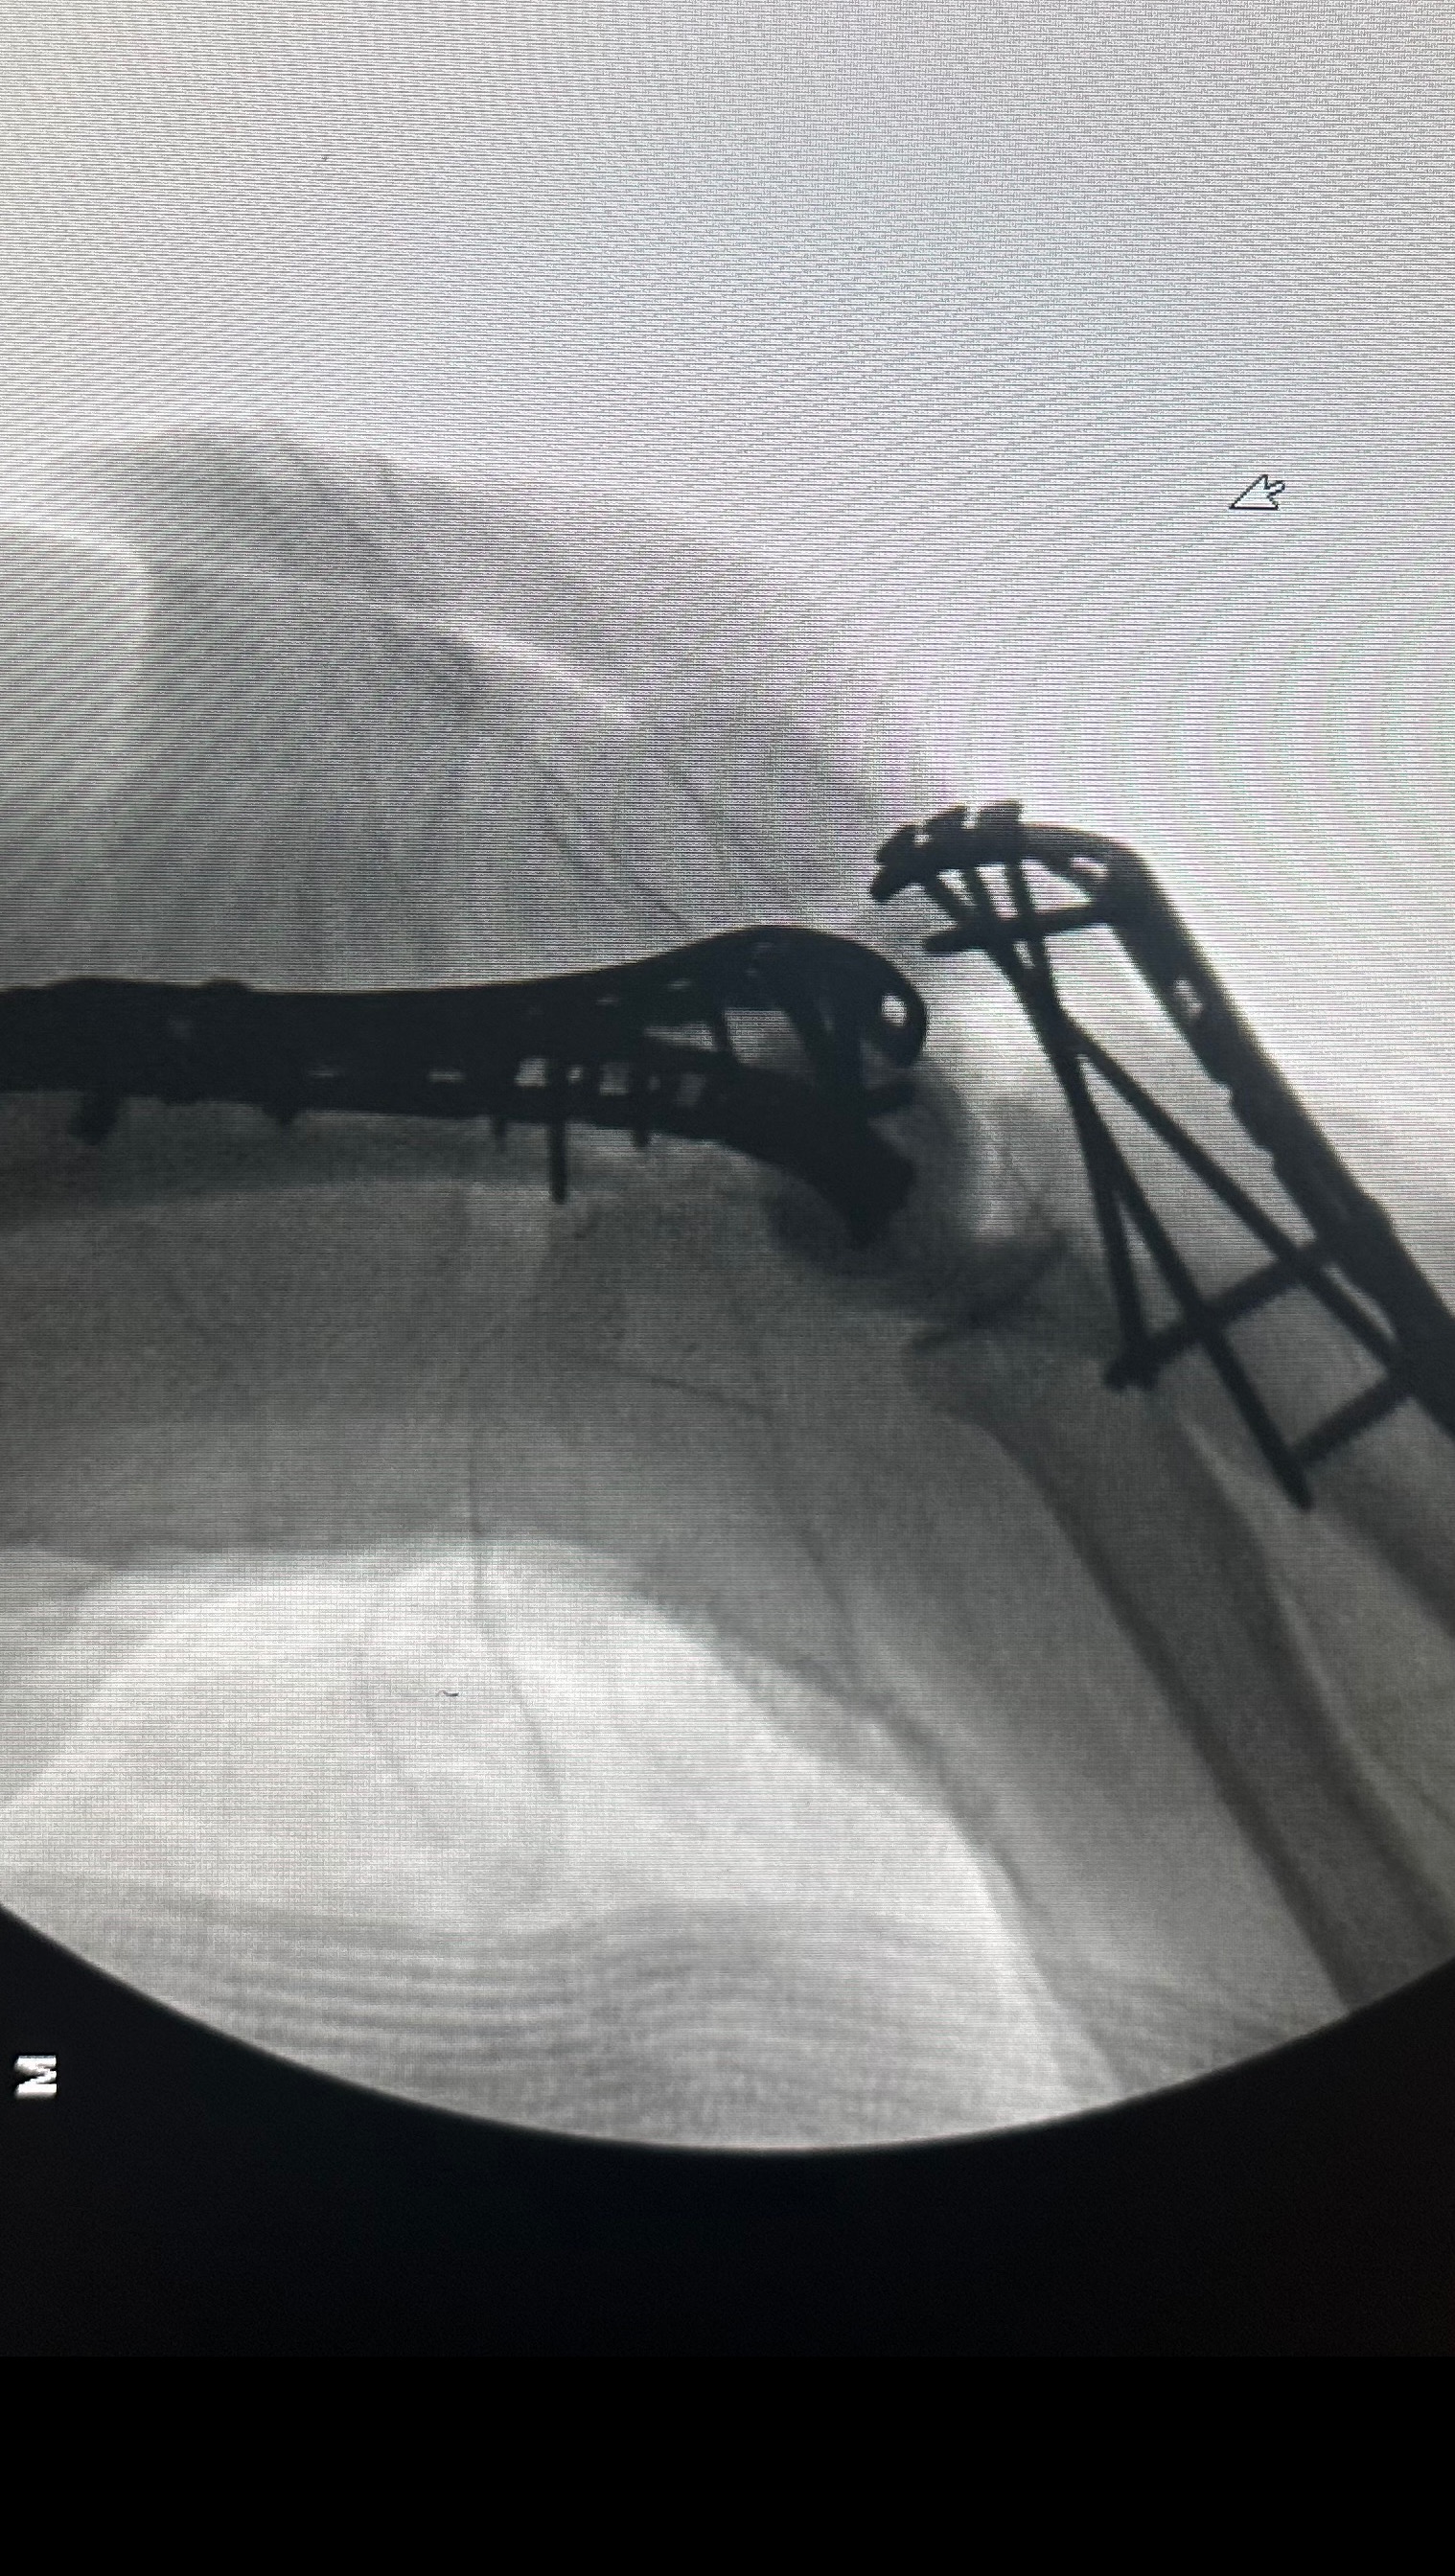

Tyler broke his Hip, Elbow, (bone is sticking out ) and he Broke his vertebrae T7-T11

he has had his surgeries on his spine, hip and elbow.